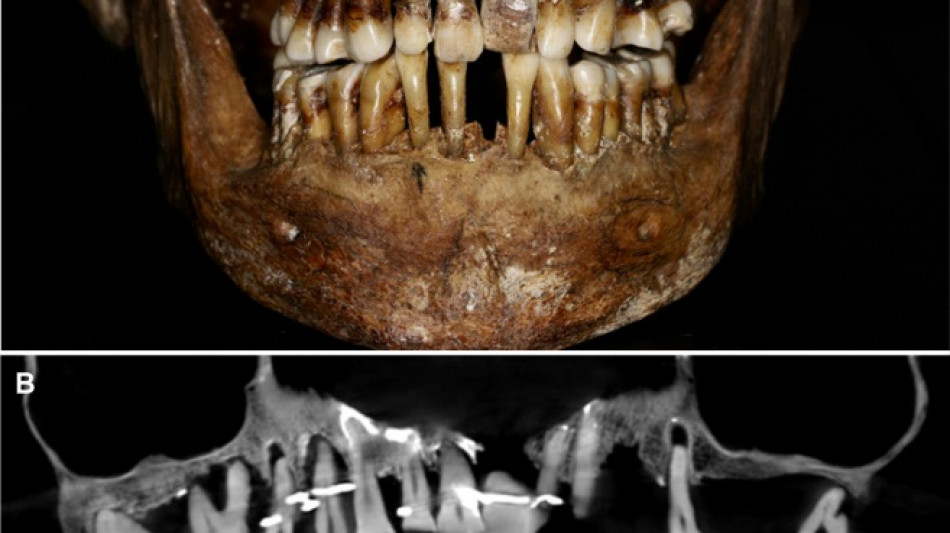

French aristocrat's golden dental secret revealed 400 years on / Photo: Handout - INRAP/Rozenn Colleter/AFP/File

Embalmed in a lead coffin, her skeleton -- and teeth -- were remarkably well preserved.

Thirty-five years later, a team of archaeologists and dentists have identified that d'Alegre suffered from periodontal disease that was loosening her teeth, according to a study published in the Journal of Archaeological Science: Reports this week.

A "Cone Beam" scan, which uses X-rays to build three-dimensional images, showed that gold wire had been used to hold together and tighten several of her teeth.

She also had an artificial tooth made of ivory from an elephant -- not hippopotamus, which was popular at the time.